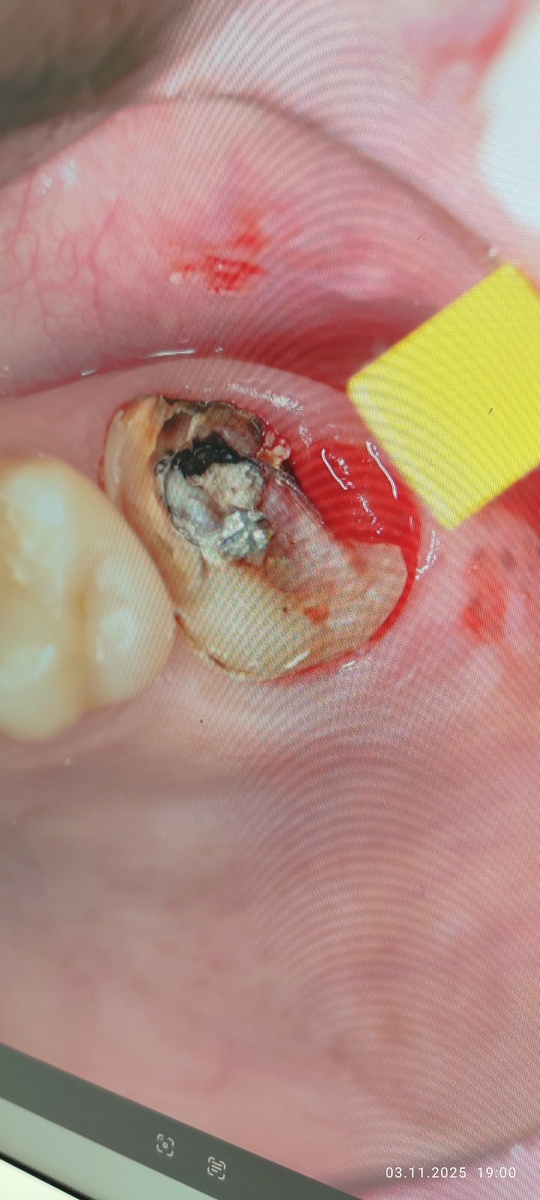

Фото не для слабонервных!!!Я сама когда увидела, обалдела.

Короче... Показываю что было далее... При снятии металлической штампованной коронки было видно что спасать нечего... Один кусок зуба просто висел...

Доктор нечаянно повредила щеку, так как очень сложно было работать на верхней 7ке... Места очень мало. Рядом с жёлтой штучкой видно красное пятно,это пролежень!!! Ткань которая пострадала от давления, вот она видимо и болела. Больше нечему.